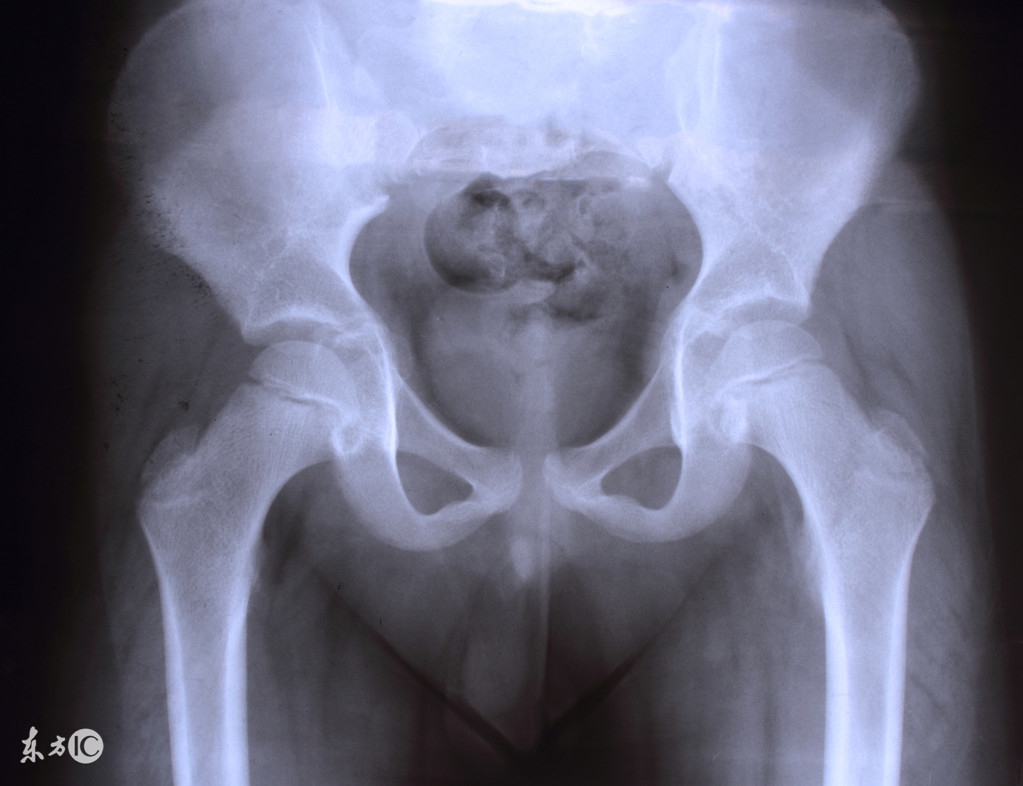

盆腔积液是盆腔存在炎性渗出物,可发生在子宫内膜发炎后,内膜策划肿胀的细胞中渗出的略黏稠的液体,被周围策划包裹所渐渐形成的囊性包块。“盆腔积液是一种表现而不是一种疾病,有很多疾病的发生都会表现为盆腔积液。”吴素慧说。

女性腹膜腔内有肠管、大网膜、子宫、输卵管、卵巢、肝脏等脏器,这些脏器位于腹膜内位器官。腹膜覆盖腹腔脏器及盆腔与腹腔表面,腹膜可漏出少量液体,称为腹膜漏出液。这样的漏出液多为淡黄色,稀薄透明,可避免腹膜腔内的脏器相互粘连,对肠道蠕动起润滑作用。正常情况下,腹腔漏出液一般少于200ml,盆腔是腹膜腔的一部分,站立时处于低位,卧位时子宫、直肠凹处于腹膜腔的最低位。因此,超声检查时可见子宫直肠凹内有液性暗区,也称为盆腔积液。

“妇科门诊多见的盆腔积液,实际上为正常生理现象,不必惶恐。”吴素慧告诉记者,盆腔积液可分为生理性盆腔积液和病理性盆腔积液两种。女性在排卵时,由于卵泡液的排出及排卵创口的渗血,这时积液量可有所增加。有时甚至可在超声检查时见到排卵,此时盆腔积液量也会有所增加。这种腹膜漏出液以及排卵产生的卵泡液等,均可导致盆腔积液,这种积液属于正常的生理现象,不需要治疗。